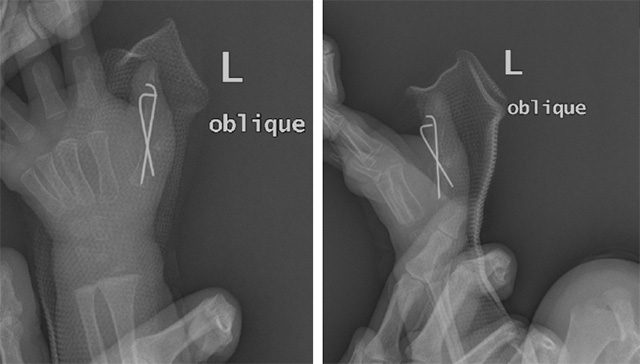

下圖為患兒1術(shù)后影像學(xué)資料

下圖為患兒2的術(shù)后影像學(xué)資料